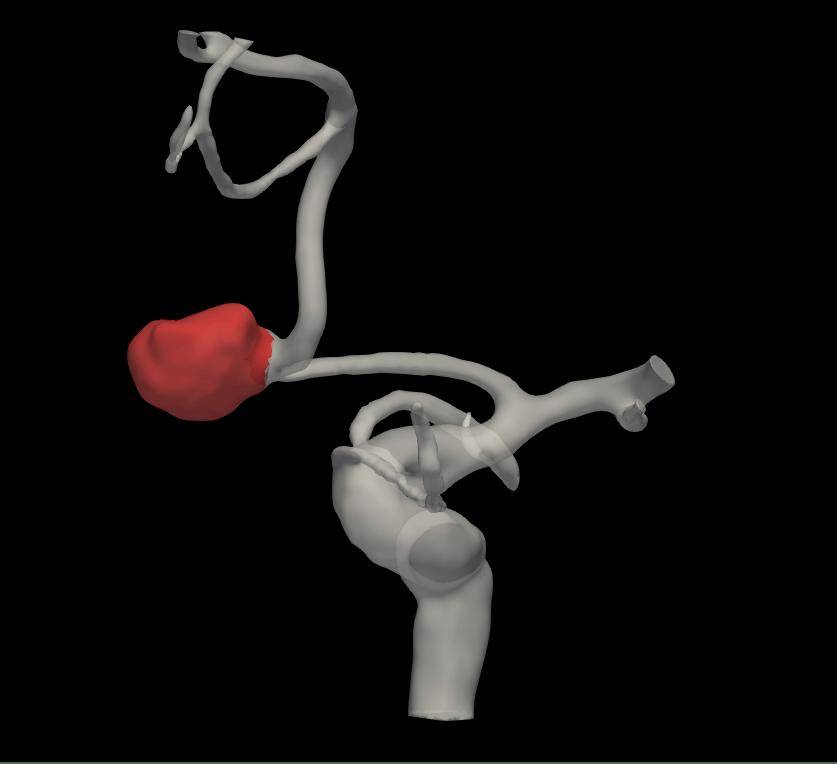

手术前,老张的脑血管造影数据被输入AI辅助系统,它迅速完成了脑部血管的三维高清重建,将错综复杂的血管结构清晰、立体地呈现出来。它不只展现图像,更进行了深度分析:AI技术自动分割动脉瘤最优瘤颈曲面,精准勾勒形态边界,并测量瘤体的大小以及与周围每一支血管的角度、距离。对于传统方式依赖个人经验的测量,AI系统提供了客观的数据支持。

图1:术前血管造影还原